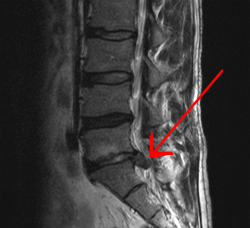

|

A spinal disc herniation demonstrated via MRI. | |